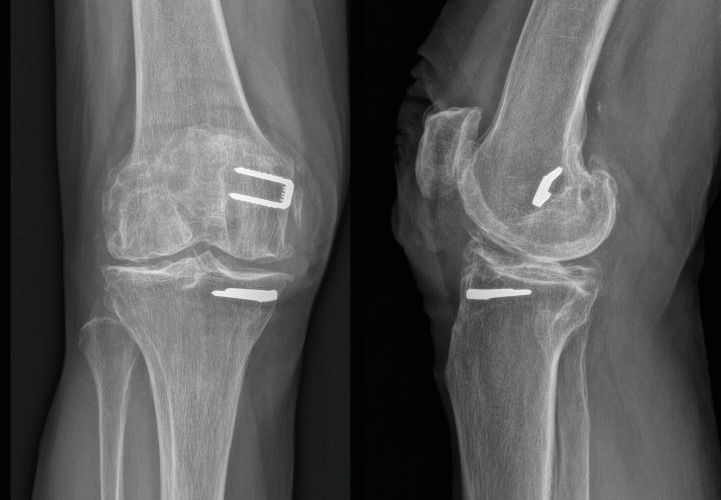

Technique Prothèse totale de genou avec matériel en place , Florian Boureau Alpilles Luberon Orthopédie, 1037 Av. Pierre Mendès France, 84300 Cavaillon, France 🖂 docteur.boureau@gmail.com N°322 - Mars 2023 ● 11 min de lecture